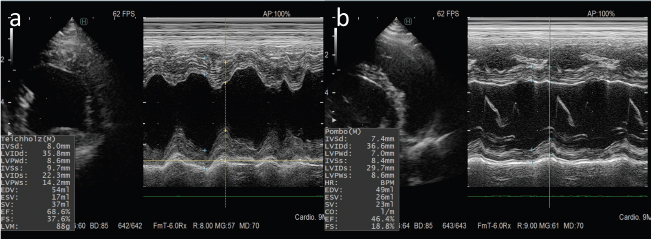

An 8-year-old, castrated, mixed-breed dog weighing 14.2 kg was referred to the Veterinary Medical Center, Obihiro University of Agriculture and Veterinary Medicine, for investigation of superficial lymph node enlargement for 1 month. Based on cytological findings and clonality analysis (Lana et al., 2006), the dog was diagnosed with multicentric high-grade B-cell lymphoma, clinical stage V (sub-stage b). The dog received l-asparaginase (5,000 IU/m2, SC) for induction, which was complicated by tumor lysis syndrome. After recovery from tumor lysis syndrome, treatment with 25-week multi-agent chemotherapy (Garrett et al., 2002), which consisted of vincristine (0.5 mg/m2, IV), cyclophosphamide (250 mg/m2, IV), doxorubicin (25 mg/m2, IV), and prednisolone (2 mg/kg, PO, q24h), was administered from April to October 2018 (Fig. 1). The patient achieved complete remission and was doing well, but the lymphoma relapsed 6 months after first-line chemotherapy. Reinduction was attempted using the same protocol from April to October 2019, which replaced third and fourth doxorubicin with mitoxantrone because of the risk of cumulative toxicity of doxorubicin. The cumulative doxorubicin dose was 125 mg/m2. Before second doxorubicin, echocardiographic examination was performed, showing normal cardiac function with an estimated left ventricular ejection fraction (LVEF) of 68.6% and left ventricle fractional shortening (LVFS) of 37.6% (Fig. 2a). In addition, diastolic and systolic left ventricular wall thicknesses were 8.6 and 14.2 mm, respectively. A mitoxantrone dose of 4 mg/m2 was administered twice. The dog achieved a second complete remission, but relapsed again 6 months after second-line chemotherapy. Subsequently, the dog received third-line chemotherapy, including epirubicin (25 mg/m2, IV) and vincristine, resulting in high cytocidal effects. One week after five cycles of epirubicin (cumulative epirubicin dose, 125 mg/m2), the dog was admitted to the hospital with a history of orthopnea, swelling of legs, and fatigue. On physical examination, muffled heart sounds were identified. Thoracic radiographs revealed generalized cardiomegaly (Fig. 3), and vertebral heart size was 11.5 (normal range, 9.7 ± 0.5 vertebrae). Electrocardiography (ECG) showed accelerated idioventricular rhythm with a wide QRS complex (Fig. 4). Echocardiography revealed severe diffuse hypokinesia with an LVEF of 46.4% and LVFS of 18.8% (Fig. 2b), and reduced diastolic and systolic left ventricular wall thickness (7.0 and 8.6 mm, respectively). Troponin I was 1.185 ng/ml (FUJIFILM VET Systems, Tokyo, reference range; 0.006–0.129 ng/ml). Based on these findings, a diagnosis of anthracycline-induced cardiomyopathy (AICM) was established. The dog was treated with benazepril (0.32 mg/kg, PO, q24h) and pimobendane (0.16 mg/kg, PO, q12h). Seven days after the treatment for cardiomyopathy, the dog was clinically stable, and echocardiography revealed improved cardiac function with LVEF of 66.2% and LVFS of 30.4%. However, after 9 days, the condition worsened, and a large number of lymphoblast cells were observed in the peripheral blood smear of the dog. Cytosine arabinoside (300 mg/m2, IV, drip infusion for 3 hours) was administered, but the dog subsequently died 22 days after the diagnosis of cardiomyopathy. Necropsy was not performed.

Fig. 2. M-mode echocardiograms of the case. (a): Normal cardiac function was seen in six cycles of doxorubicin administration. (b): A marked reduction in ventricular contractility was observed at 1 week after administration of six cycles of epirubicin.